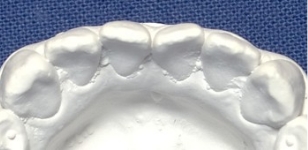

安定調査症例3

高さも不揃いでした。

歯ぐきも良くなった。

なったが変化は僅かだった。